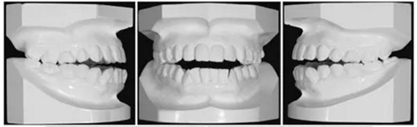

面部照片顯示,患者為凸面型,鼻唇時頦肌緊張(Figure 3)。口內(nèi)檢查顯示雙側(cè)第二前磨牙間開合(Figures3 and 4)。覆合覆蓋分別為-3.5mm和+1.2mm。正面觀,上下牙列中線與面部中線一致。雙側(cè)磨牙II類關(guān)系,下前牙區(qū)中度擁擠。

全景片顯示四顆智齒都存在,上頜切牙有牙根吸收,并且在雙側(cè)髁突都有相當(dāng)大的吸收(Figures 1B and 5A)。頭測分析顯示:ANB angle, 4.5°; FMA, 46.7°; U1-SN, 95.8°; L1-MP, 83.7°(Table 1, Figure 5B)。

基于上述檢查結(jié)果,患者被診斷為雙側(cè)髁突形態(tài)改變引起的開合畸形。